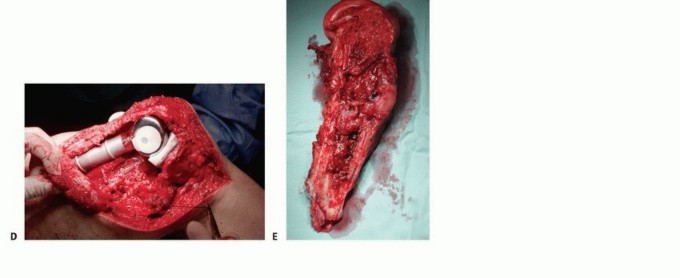

الشكل 1: أ. صورة أشعة سينية تظهر ورمًا نقيليًا في الحُق الأيمن لدى رجل يبلغ من العمر 72 عامًا ولديه تاريخ معروف بسرطان الغدة الدرقية. ب. يظهر التصوير المقطعي المحوسب (CT) تدميرًا واسعًا للعظام وامتدادًا للأنسجة الرخوة. محاولة الاستئصال بناءً على النتائج الشعاعية وحدها قد تؤدي إلى استئصال جزئي للآفة ونزيف محتمل بسبب الأوعية الدموية الكثيفة لهذا الورم. بالنظر إلى هذه النتائج الشعاعية، خضع هذا المريض لانسداد وعائي قبل الجراحة مما قلل من فقدان الدم أثناء الجراحة وسمح باستئصال ناجح.

إذا كانت النقيلة قيد الفحص تقع في عظم طويل، فيجب أيضًا إجراء صور أشعة سينية ذات جودة معقولة لكامل امتداد العظم لاستبعاد وجود نقائل إضافية؛ لأن هذه البيانات حاسمة للتخطيط الجراحي. قد تتسبب النقائل التي لم تُكتشف في كسور مرضية عند تحمل الوزن بعد الجراحة وتتطلب جراحة واسعة لإصلاحها.